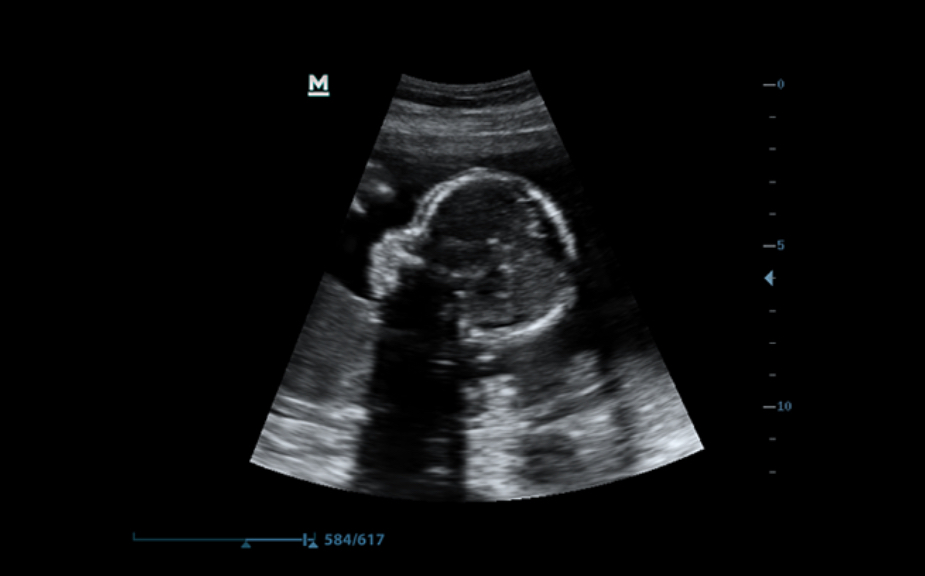

iLive

Al integrar un algoritmo de proyecciĂłn de rayos con una nueva modalidad de iluminaciĂłn virtual, iLive genera imĂĄgenes increĂblemente reales del feto con una piel de apariencia humana.

Smart Face

El nuevo Z50 proporciona una optimizaciĂłn rĂĄpida e inteligente del rostro del feto con una simple operaciĂłn de un solo toque. Puede eliminar de forma inmediata las oclusiones en los datos de volumen, excluir el ruido no deseado y generar una visiĂłn Ăłptima del rostro fetal con un mĂnimo de esfuerzo.

Smart OB

MediciĂłn automĂĄtica de parĂĄmetros fetales: es posible trazar y calcular los parĂĄmetros BPD, OFD, HC, HUM, AC y FL con un solo clic.